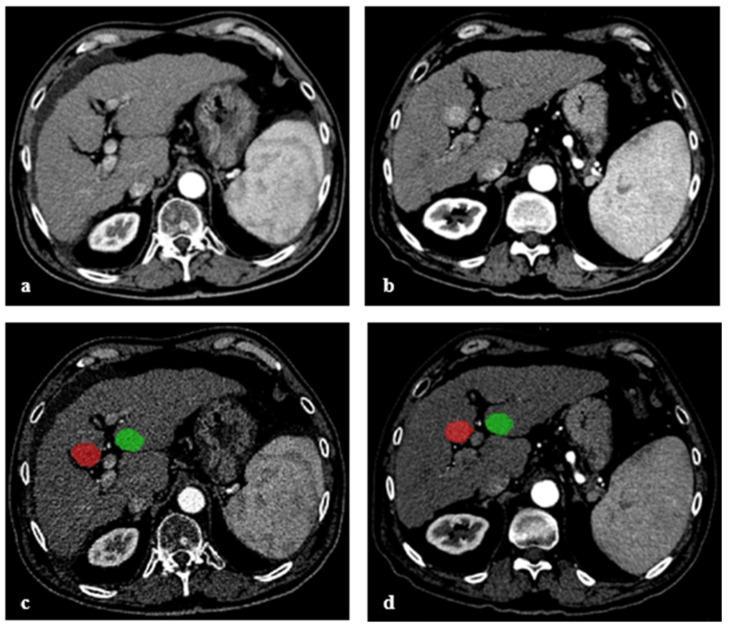

Liver cirrhosis poses a major risk for the development of hepatocellular carcinoma (HCC). This retrospective study investigated to what extent radiomic features allow the prediction of emerging HCC in patients with cirrhosis in contrast-enhanced computed tomography (CECT). A total of 51 patients with liver cirrhosis and newly detected HCC lesions ( = 82) during follow-up (FU-CT) after local tumor therapy were included. These lesions were not to have been detected by the radiologist in the chronologically prior CECT (PRE-CT). For training purposes, segmentations of 22 patients with liver cirrhosis but without HCC-recurrence were added. A total of 186 areas (82 HCCs and 104 cirrhotic liver areas without HCC) were analyzed. Using univariate analysis, four independent features were identified, and a multivariate logistic regression model was trained to classify the outlined regions as "HCC probable" or "HCC improbable". In total, 60/82 (73%) of segmentations with later detected HCC and 84/104 (81%) segmentations without HCC were classified correctly (AUC of 81%, 95% CI 74-87%), yielding a sensitivity of 72% (95% CI 57-83%) and a specificity of 86% (95% CI 76-96%). In conclusion, the model predicted the occurrence of new HCCs within segmented areas with an acceptable sensitivity and specificity in cirrhotic liver tissue in CECT.

肝硬化是肝细胞癌(HCC)发生的主要危险因素。这项回顾性研究调查了在对比增强计算机断层扫描(CECT)中,放射组学特征在多大程度上能够预测肝硬化患者新发HCC。本研究纳入了51例肝硬化患者,这些患者在局部肿瘤治疗后的随访(FU-CT)期间新发现了HCC病变(n = 82)。这些病变在之前按时间顺序排列的CECT(PRE-CT)中未被放射科医生检测到。为了进行训练,增加了22例无HCC复发的肝硬化患者的分割图像。总共分析了186个区域(82个HCC和104个无HCC的肝硬化肝区)。通过单因素分析,确定了四个独立特征,并训练了一个多因素逻辑回归模型,以将勾勒出的区域分类为“可能为HCC”或“不太可能为HCC”。总体而言,后来检测到HCC的分割图像中有60/82(73%)被正确分类,无HCC的分割图像中有84/104(81%)被正确分类(AUC为81%,95%CI为74-87%),敏感性为72%(95%CI为57-83%),特异性为86%(95%CI为76-96%)。总之,该模型在CECT中对肝硬化肝组织分割区域内新发HCC的发生具有可接受的敏感性和特异性。